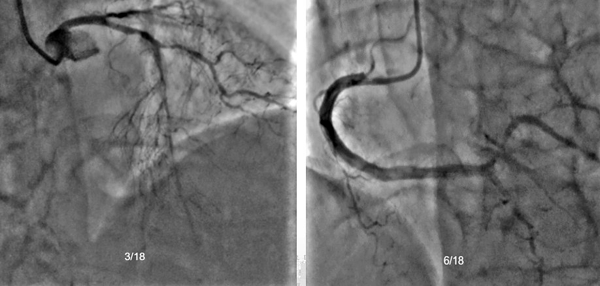

86岁的王阿姨(化名)数天前在家中摔倒导致髋部骨折,在当地住院时发生急性心肌梗死,考虑病情危重复杂,未能进行骨科手术治疗。由于患者病情较重,我院心内科迅速将患者收入CCU,刘巍团队成功为患者开通病变冠状动脉并植入支架1枚。既已完成冠脉血运重建,髋部骨折手术成为当务之急。急性心肌梗死是外科择期手术的禁忌。患者正在接受双联抗血小板治疗,此时手术将面临极大的缺血和出血风险。摆在心内科和创伤骨科团队面前的问题是如何为这样一名高龄患者安全地进行股骨颈骨折手术。

(左)造影可见前降支血管近端95%狭窄;(中)于前降支病变处植入支架1枚;(右)支架植入后再次造影显示近端血管恢复通畅。

经过心内科、创伤骨科以及麻醉团队会诊研究,在评估围术期缺血和出血风险后,决定围术期继续应用阿司匹林加低分子肝素治疗方案。患者在入院8天后手术,麻醉科成功实施了腰椎管内麻醉,创伤骨科进行了右侧股骨粗隆骨折闭合复位髓内针固定手术,手术过程顺利,出血量只有50ml,术后转入CCU继续监测、调理。术后患者麻醉恢复后即可在床上随意活动,也可以逐渐下地站立或行走。围术期内无心肌缺血症状发作,监测心电图无动态改变,心肌酶回落趋于正常。李庭团队成员每日对患者进行会诊,与患者交流病情,指导术后注意事项,力争让骨折部位加快康复。患者病情一天天好转,很快便开始下床活动,术后第5天顺利出院。